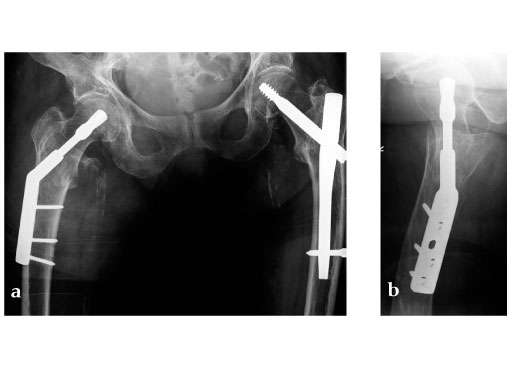

Ten pairs of human cadaveric femora were used. Left and right bones of every femoral pair were randomly instrumented with either a DHS blade or a DHS using 4-hole side plates. Tip-apex distance was standardized to 10 mm. After implantation an unstable type 31-B2 fracture (Fig 1) was created using a custom-made saw guide. Cyclic loading was performed to the femoral head applying load trajectories as measured in vivo in total hip replacement (THR) patients (Bergmann et al., 2001). The passive function of the iliotibial band was simulated by a cable. Starting at 1500 N the peak load was increased by 500 N every 5000 cycles until cut-out or complete failure of the construct. X-rays were taken at 5000 cycle intervals. A survival analysis was performed based on the numbers of cycles until cut-out, defined as the first visible implant migration as determined from x-rays.

With the applied loading regime a total of 100% cut-outs occurred in the DHS group compared to 50% in the DHS blade group. The survival probability in terms of cut-out resistance was significantly higher for the DHS blade (Fig 2) (P=.023).

Based on the data available, we conclude that the DHS blade performs superior compared to the DHS in terms of cut-out resistance under cyclic loading. This might be due to cancellous bone compaction around the helical blade during implant insertion (Fig 3), which should be investigated in further studies. This in vitro study supports the usage of the DHS blade in order to reduce the cut-out rate in treatment of unstable femoral neck fractures.

Müller AO Classification type 31-A2 fracture in an 83 year-old female with severe osteoporosis.